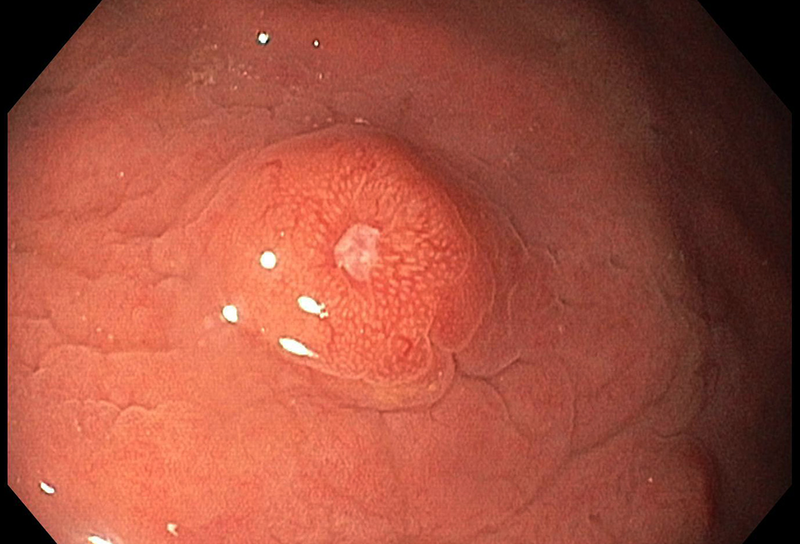

A 67-year-old male underwent endoscopic evaluation of the upper gastrointestinal tract after diagnosis of peritoneal carcinomatosis in the setting of unknown primary on CT scan (CUP syndrome). Within the gastric corpus, MULTIPLE nodular (sub)mucosal lesions, some of which with volcano-like central ulceration, were seen (Panels A-B). In addition to biopsy sampling, endoscopic mucosal resection (EMR) of the largest lesion was performed.